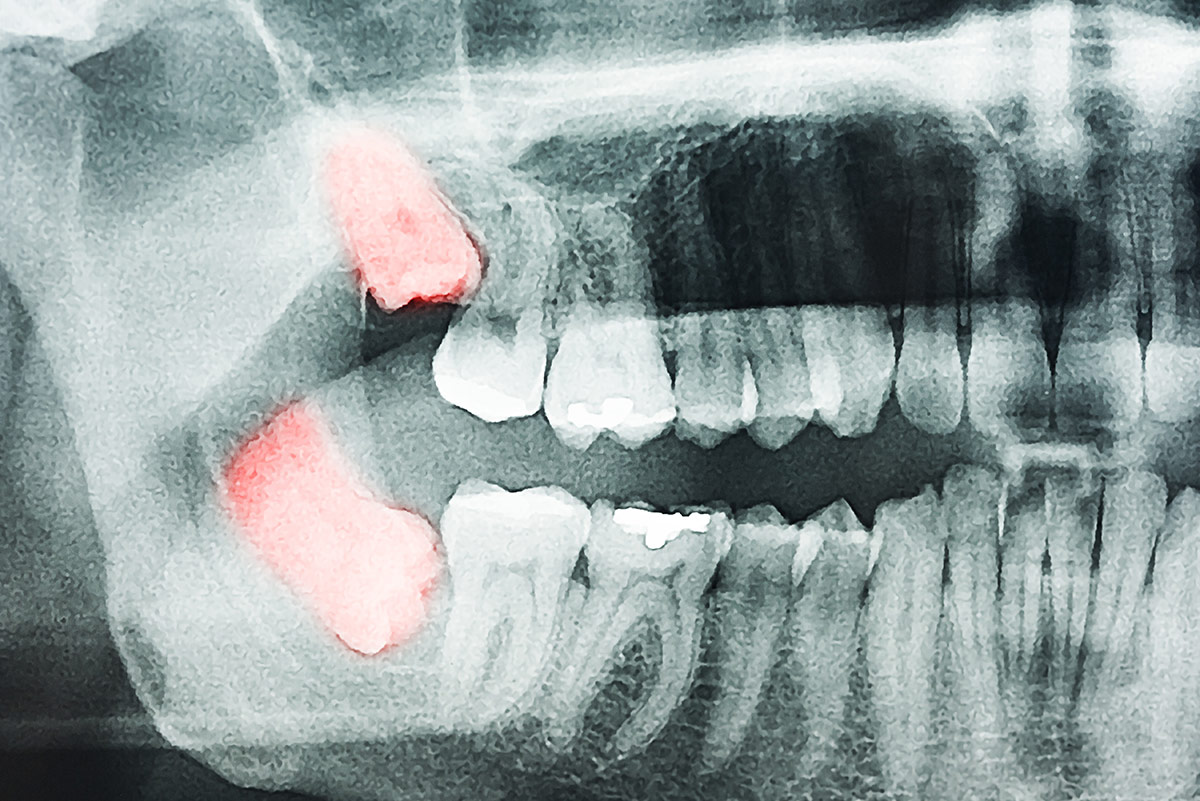

If there is no space in the jaw for the wisdom teeth to grow in, then they can become impacted as a result. This term means that the tooth has no place to move within the jaw, and then causes issues by either beginning to move in places they shouldn’t (e.g. sideways into the jaw) or becoming trapped in place within the gum, causing pain and putting the patient at risk for infection or damage to the surrounding teeth. For this reason, if wisdom teeth are impacted, receiving a tooth extraction in Vancouver, BC V6M 4B9 is recommended.

Wisdom Teeth Removal in Vancouver